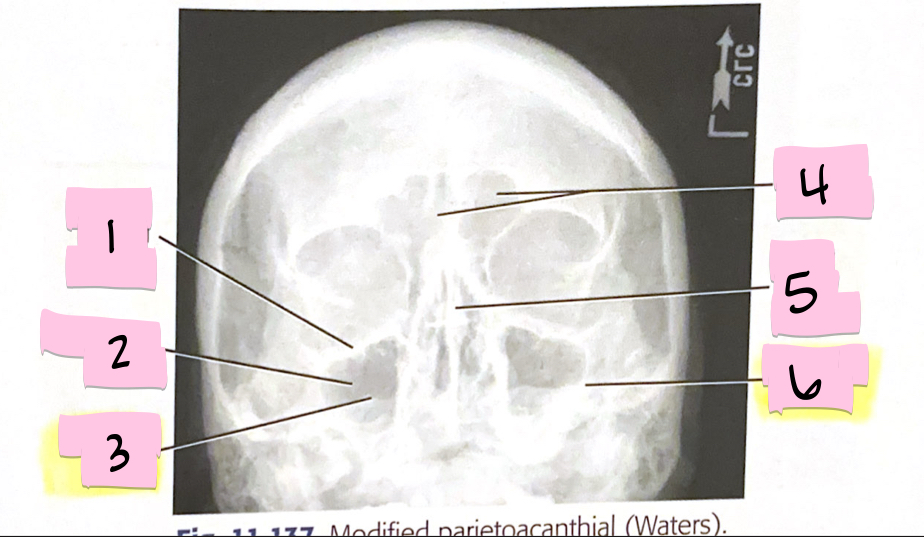

What is 1 pointing to?

Inferior orbital margin

What is 2 pointing to?

Maxillary sinus

What is 3 pointing to?

Petrous ridge

What is 4 pointing to?

Frontal sinuses

What is 5 pointing to?

Bony nasal septum

What is 6 pointing to?

Petrous ridge